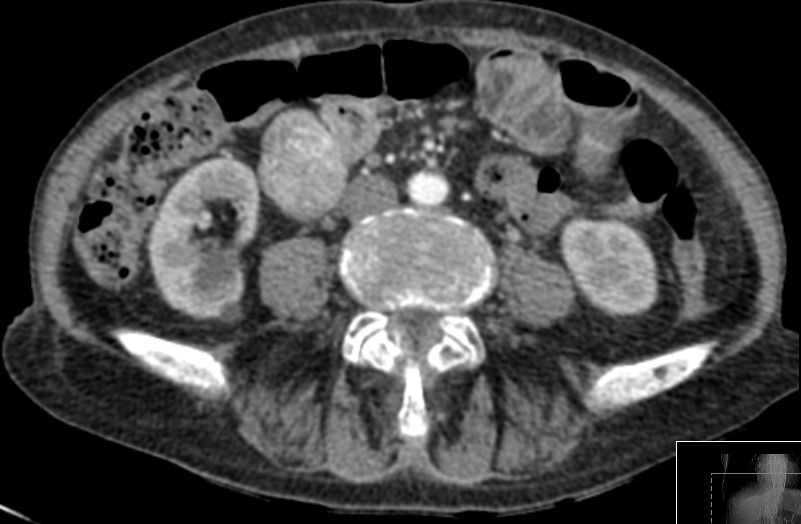

56-jähriger Mann mit großer Raumforderung der Magenvorderwand.

Gallenblase und Leber werden etwas verdrängend.

Vergrößerte Lymphknoten sind nicht nachweisbar.![]() | |||||||||||||||||||||||||||||||||||||||||